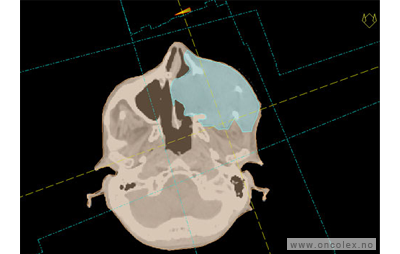

Skisse over hvordan strålefeltet planlegges:

Illustrasjon for målvolum

• GTV (Gross Tumor Volume): Identifisert tumor.

• CTV (Clinical Target Volume) GTV + omkringliggende vev hvor det kan væremikroskopisk spredning.

• ITV (Internal Target Volume): CTV + en indre margin som tar hensyn tilindre bevegelser og endringer av CTV.

• PTV (Planning Target Volume): Innstillingsmargin som inneholder ITV og samtidig tar hensyn til antatte pasientbevegelser, samt variasjoner i pasientopplegging og feltinnstillinger.

• Feltgrense. Tegnes som oftest på kroppen.